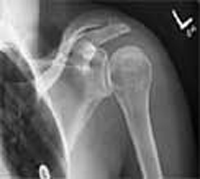

Inflamación del hombro

La inflamación del hombro es un dolor provocado por la excesiva fricción o contracción del manguito rotador y el omóplato.